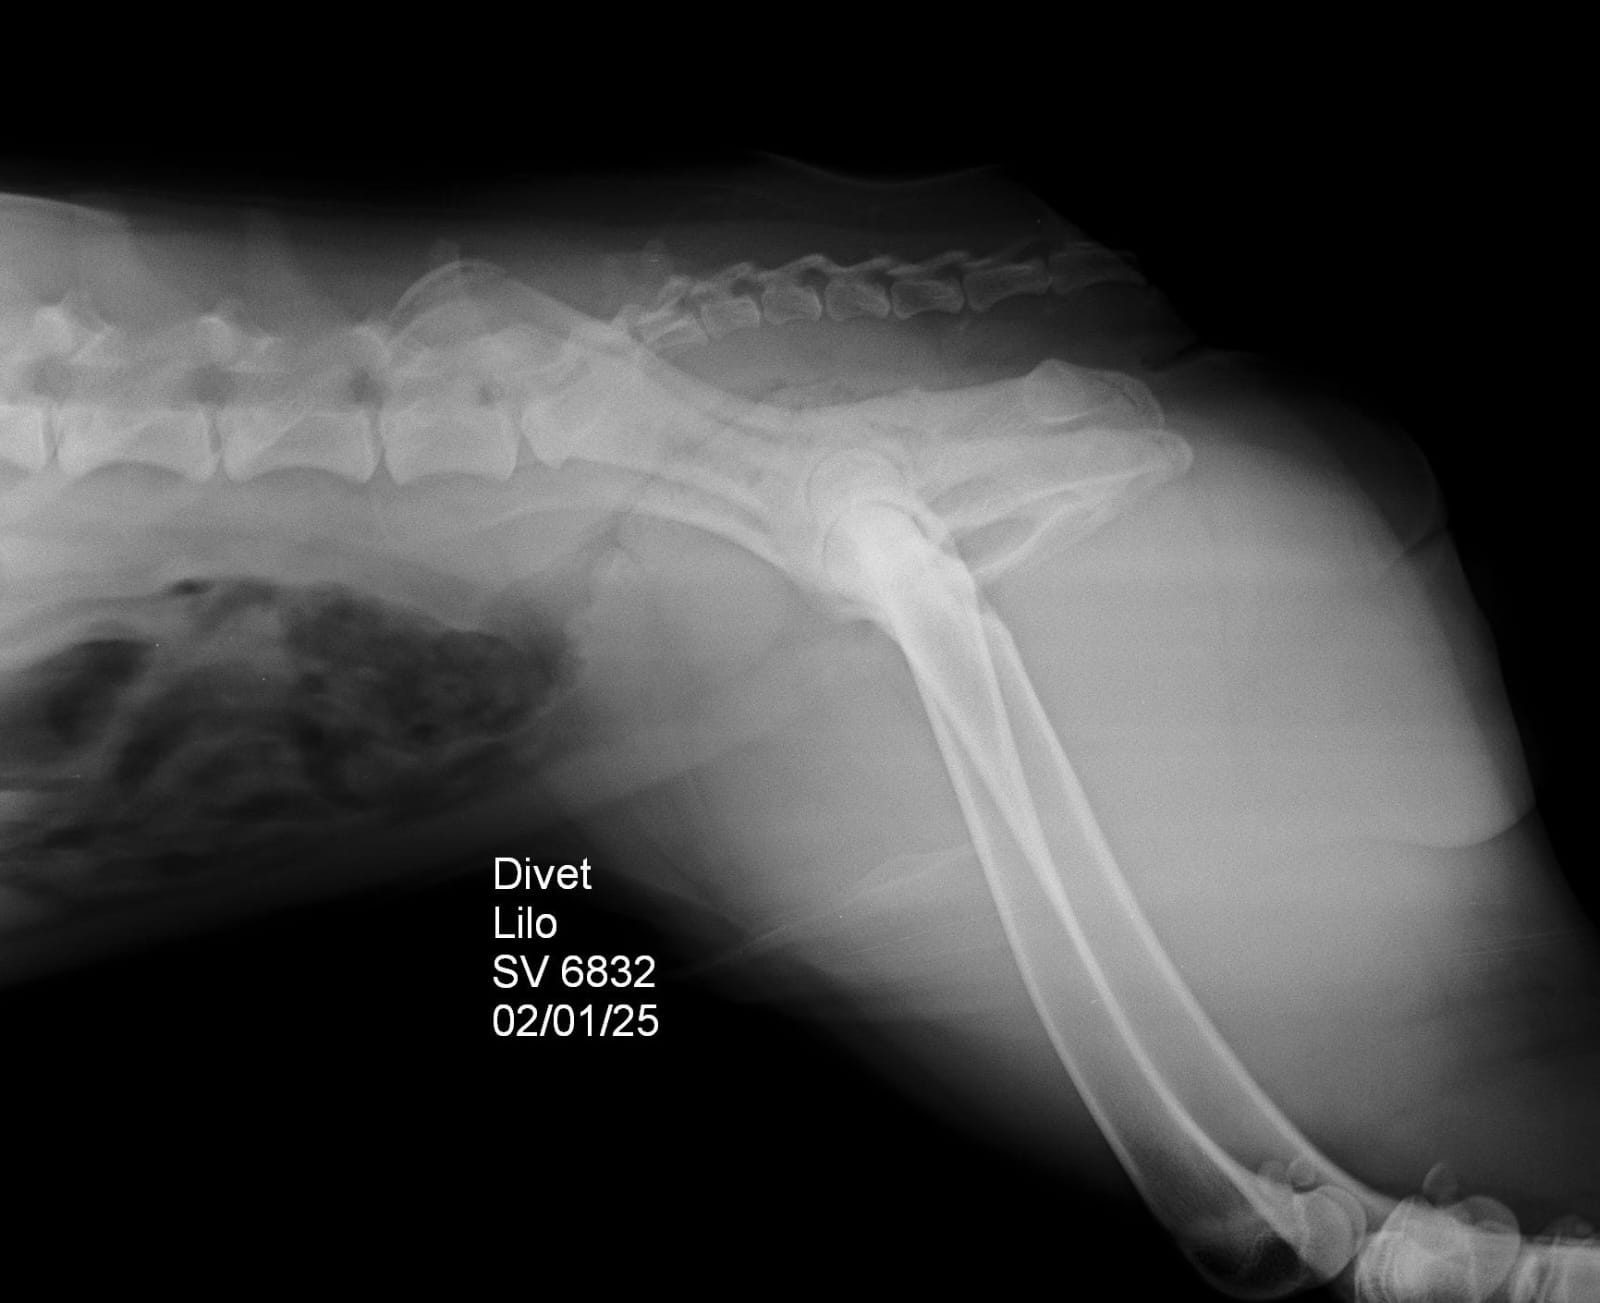

Raio X